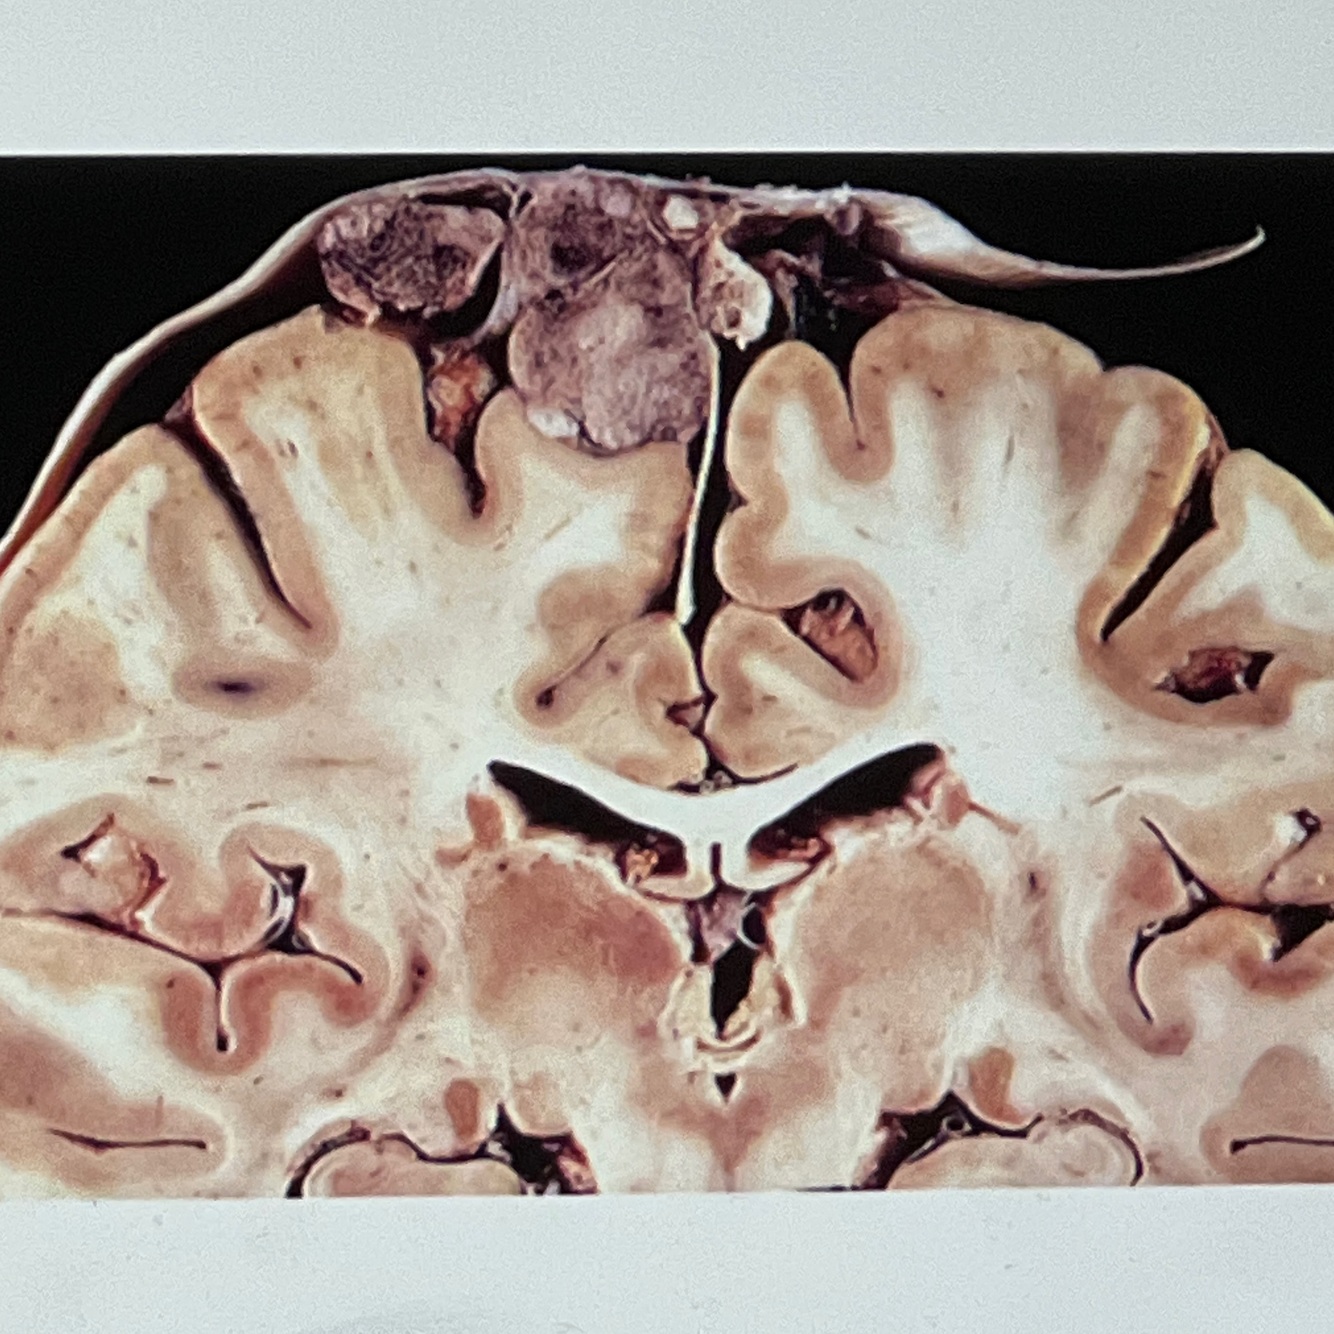

Diagnosis: intracerebral hemorrhage

Location: basal ganglia

A coronal section in the brain showing a localised area of large dark red brown hematoma in the cerebral hemisphere

Note compression effects on the ventricle

Smaller hemorrhagic foci are also seen